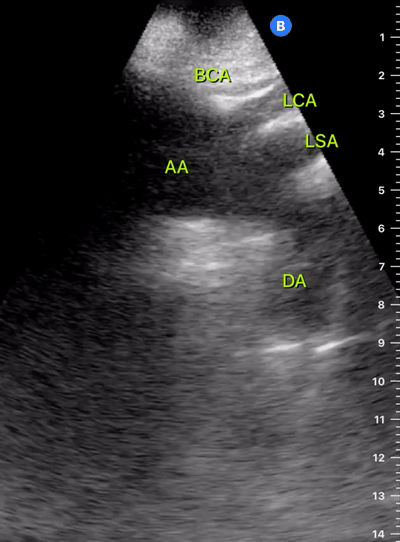

Exit: is there acute aortic root pathology?

Thoracic Aortic dissection is a time-dependent and deadly pathology that can occur silently or be masked by a variety of clinical presentations. While angio-CT remains the gold standard for diagnosis, US may be performed quicker and at the bedside. In the visible portion of the aortic root, the US findings can include intimal flap, aortic valve insufficiency, retrograde aortic flow, or rupture into the pericardium with pericardial effusion and tamponade. Alternatively, dilation of the aortic root is characteristic of a thoracic aortic aneurysm.

Importantly, remember that thoracic aortic dilation or intimal flap may occur distal to the aortic root, where an US scan is usually blind. Hence, the absence of dilation or flap does not rule out aortic disease.

THE VIEWS

The PLAX view is best for exploring the aortic root. If performed by an experienced operator, aortic root measurements in this window correlate well with angio-CT measurements.

The Aortic root size varies with age and gender and should be measured at its widest point, perpendicular to its long axis. In general, a root > 4 cm should be considered borderline and enough to warrant a formal study.

Alternatively, the aortic root size can be estimated by the rule of thirds, where in the PLAx view the size of the RV, AoR, and LA should be roughly 1:1:1.

AORTIC DISSECTION

In both of these views, US may detect an intimal flap seen as a hyperechoic linear structure within the aortic lumen that moves with each heartbeat. The visualization of a flap carries a high specificity and should prompt immediate consultation with cardiothoracic surgery; however, ultrasound sensitivity for intimal flap is significantly low, and its absence does not rule out aortic dissection.